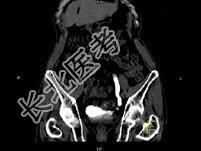

- 单项选择题男,76岁, 无痛性肉眼血尿3个月,CT检查如图所示, 下列说法错误的是 ( )

A、左侧肾盂扩张积水

B、左侧输尿管中上段扩张

C、左侧输尿管下段可见节段状不规则的软组织肿块影

D、考虑为左侧输尿管炎

E、考虑为左侧输尿管下段癌